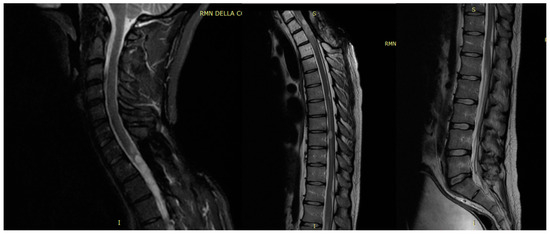

3.2. Unexpected Radiological Features in a Case of SpDG H3K27M

4.2. Radiological Finding